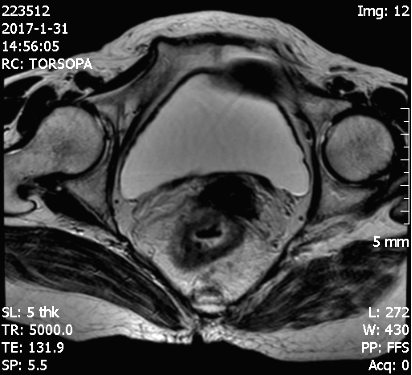

四 腹部和盆腔:主要用于腹部和盆腔的肿瘤样变,囊肿及炎性病变的诊断和鉴别诊断,是子宫、前列腺病变的首选影像学检查方法。

MRCP和MRU可无创性了解胆管和输尿管梗阻或狭窄的程度和病变性质。高分辨MRI对盆腔病变的诊断和鉴别诊断提供更多的诊断价值和依据。

高分辨磁共振对直肠癌显示及分期更清晰、直观